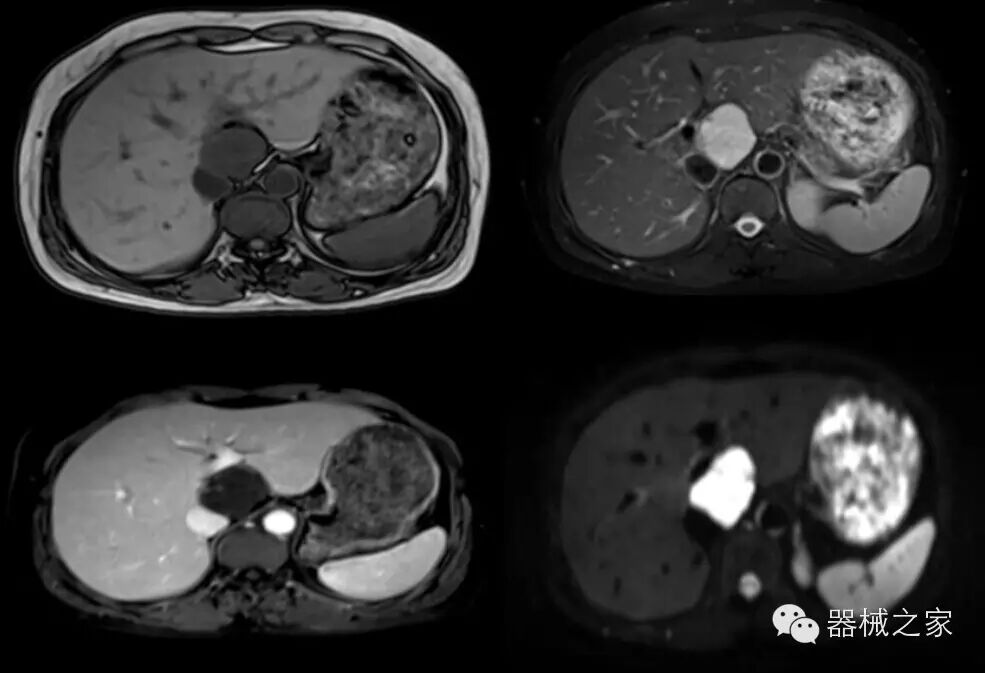

腹部组图 T1WI(Out Phased)、T2WI(FS)、THRIVE、DWI

·东软医疗于2009年研发成功中国第一台超导磁共振并获得CFDA的认证,NSM-S15P 1.5T超导磁共振系统是东软紧密围绕医院实际临床需求和科研需求而开发的一款全新产品。该产品以客户为中心设计理念,基于“Sirius天狼星”全新技术平台,具有完全自主知识产权的全数字谱仪和序列算法等核心技术,采用领先的SENSE、光纤等技术,实现了高清快速扫描,成就完美临床价值。